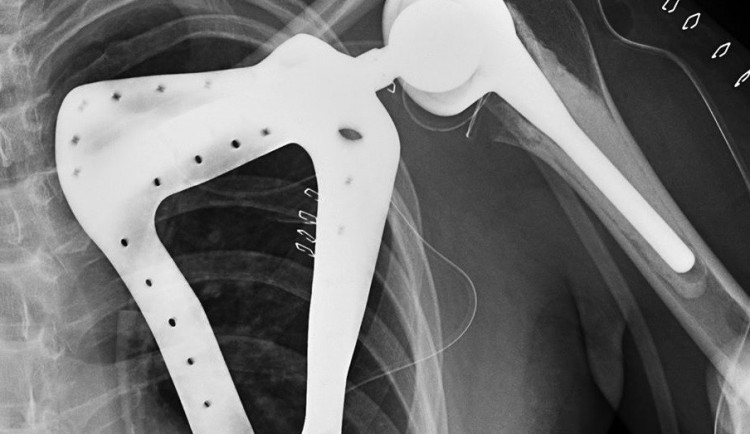

Brněnští ortopedi z Nemocnice u svaté Anny dokázali jako první v republice úspěšně provést unikátní operaci - implantaci lopatky, vč. ramenního kloubu. Operaci vedl přednosta I. ortopedické kliniky Tomáš Tomáš se svým týmem.

Paceintem svatoananeských lékařů byl teprve třiadvacetiletý mladík, jemuž před rokem odstranili celou lopatku pro nádor. Šlo se o levou končetinu s těžkým funkčním omezením a těžkým kosmetickým defektem. Mladík měl de facto nepoužitelné rameno - jeho pohyblivost byla nulová, protože hlavice pažní kosti se neměla o co opřít. Vzhledem k mladému věku pacienta se tak lékaři rozhodli jít do rozsáhlé implantace ramenního kloubu včetně lopatky.

„Operace trvala 3 hodiny, jednalo se o složitou operaci, navíc v ČR jedinečnou. Bylo nutné vypreparovat zádový sval a jím překrýt umělou lopatku,“ sdělil Tomáš Tomáš. „Náhrada lopatky byla pro pacienta vyrobena na míru, je z titanu a postříbřená z důvodu minimalizace infekce. Je vyrobena pomocí 3D tisku," doplnil.